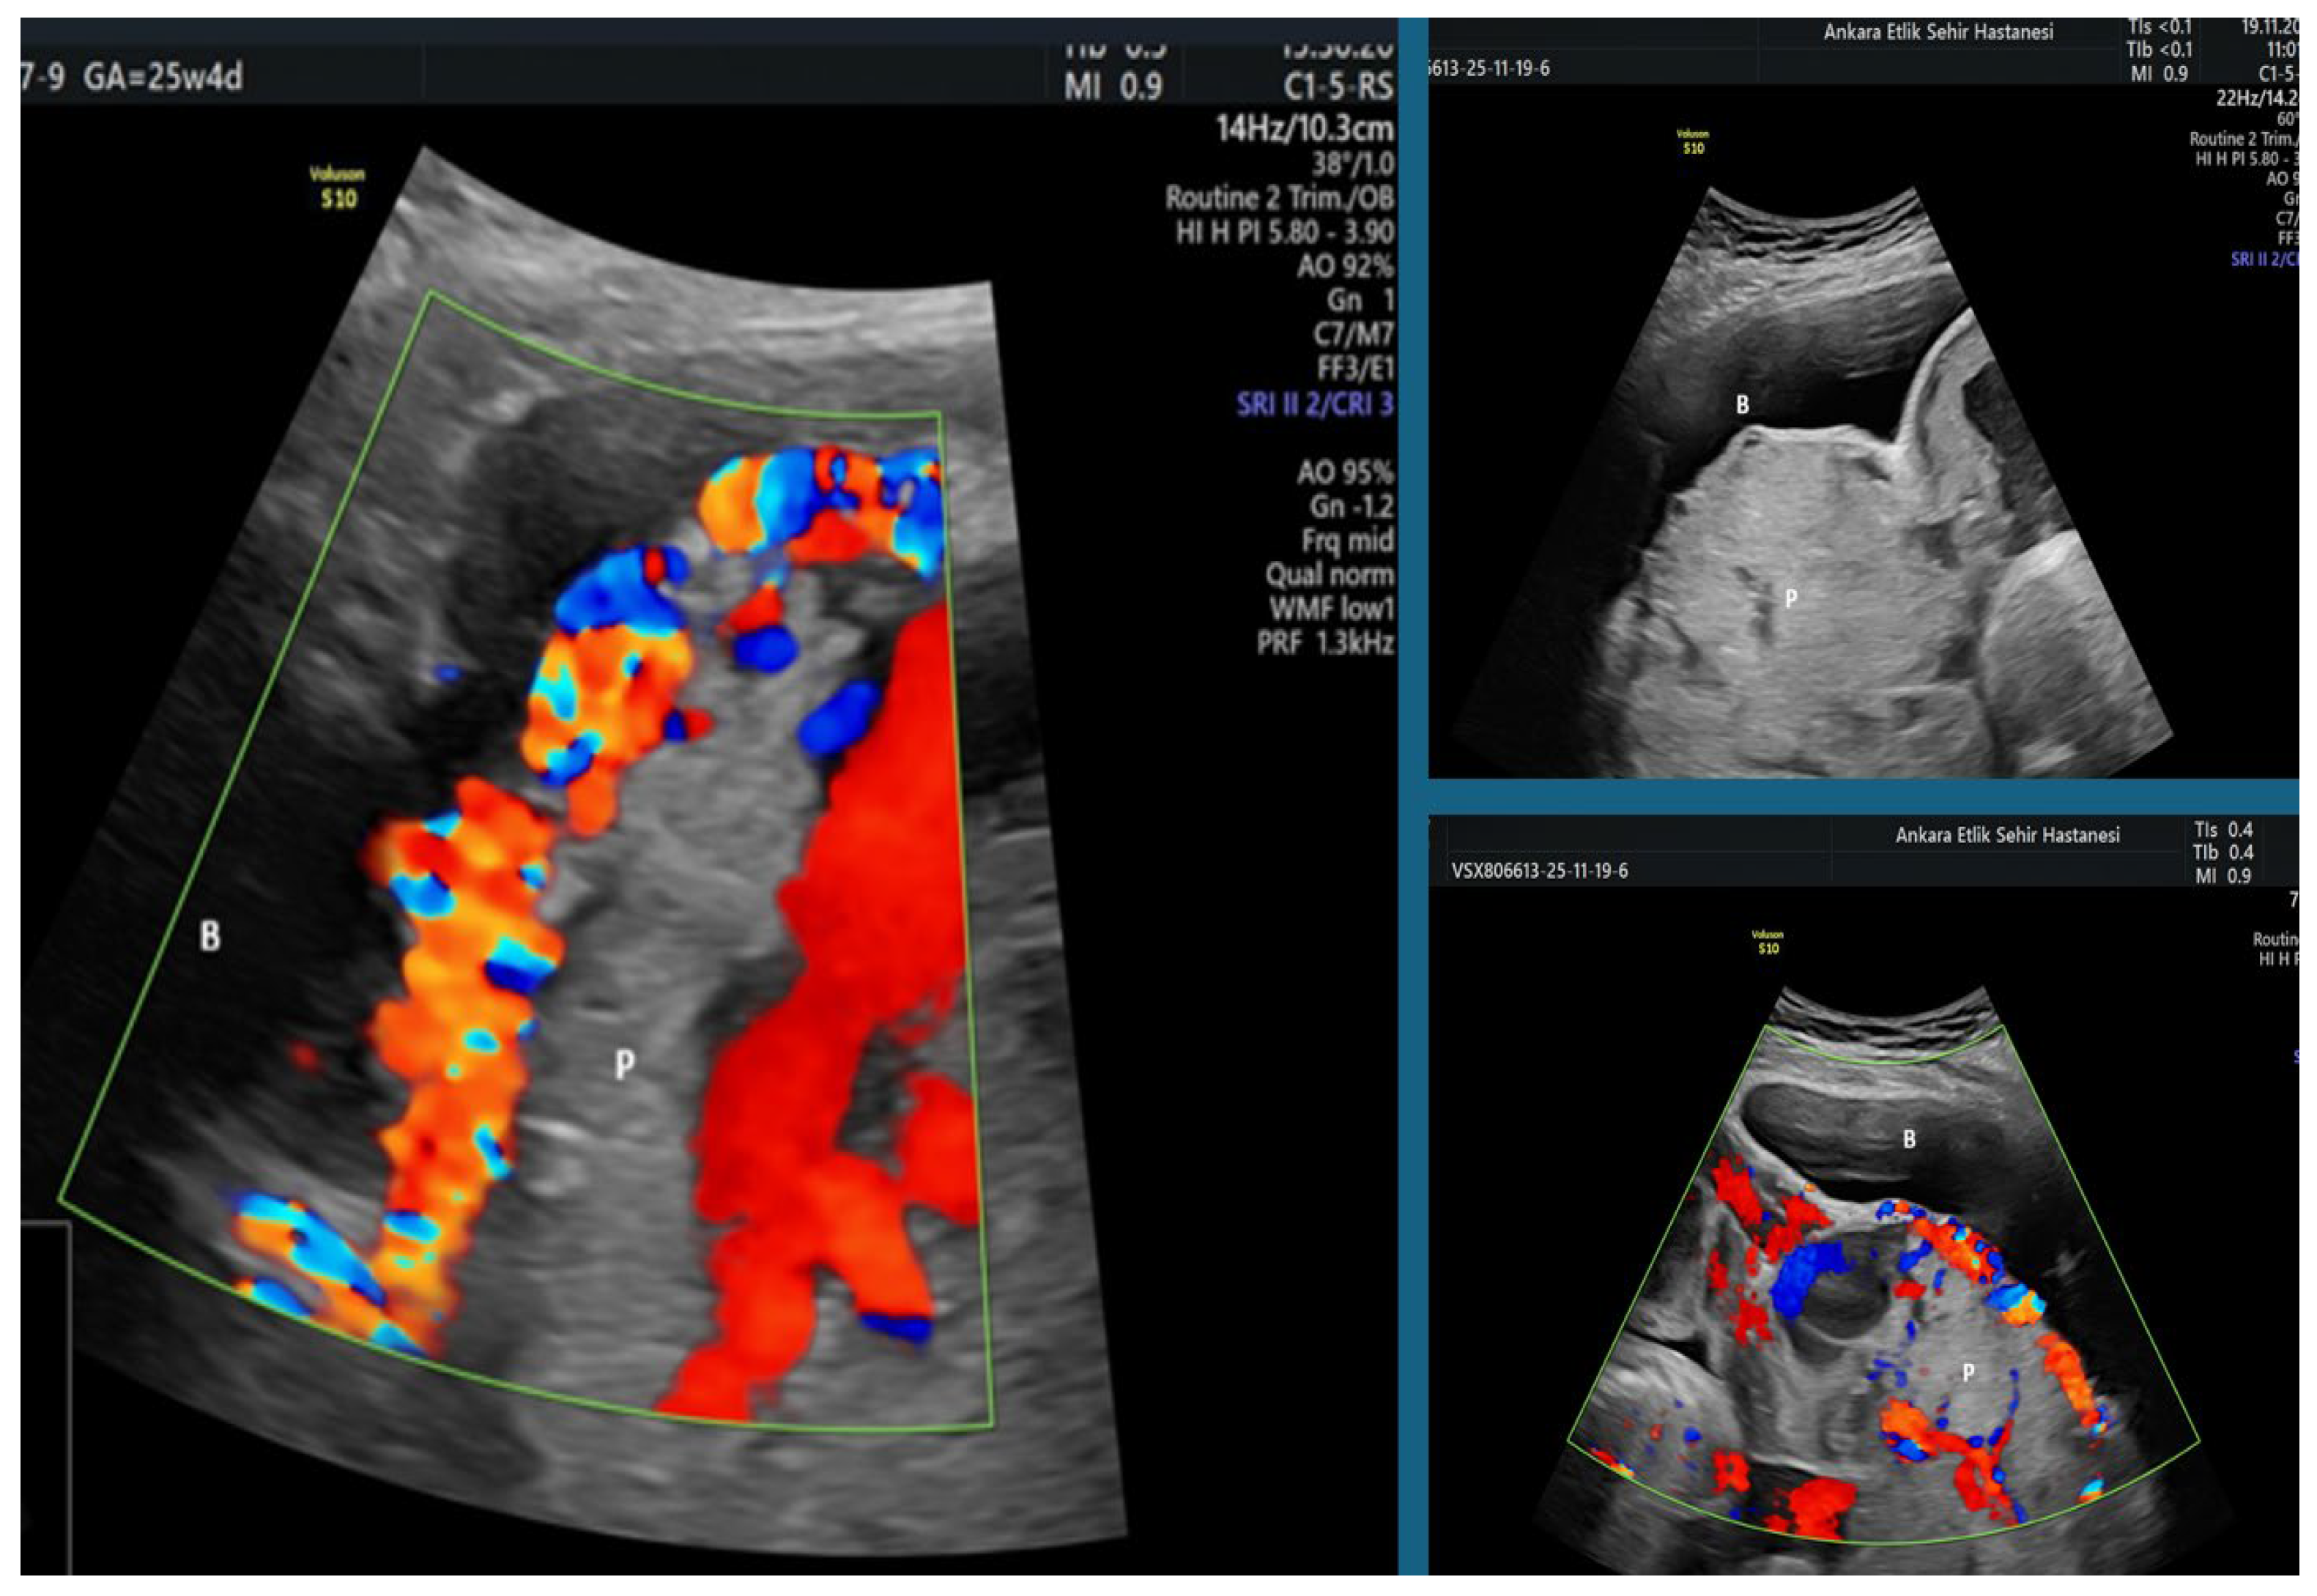

| PAS 0 | Placenta previa without hypervascularization | No abnormal placental findings; no evidence of abnormal vascularization on Doppler. |

| PAS 1 | Abnormal placental features without hypervascularization | At least two of: loss of clear zone, presence of placental lacunae, disruption of bladder wall, no hypervascularization. |

| PAS 2 | Uterovesical hypervascularization | PAS1 features plus increased vascularity between the uterus and bladder on Doppler imaging. |

| PAS 3 | Extensive parametrial vascularity | PAS1 or PAS2 features plus marked vascular extension into the parametrial region of the lower uterine segment. |